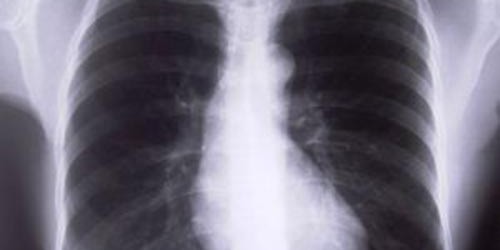

These will vary from person to person, as some affected people may will suffer from digestive problems, some from respiratory problems, and some from both. Presence of chronic respiratory infections such as chronic sinusitis, pneumonia and bronchitis is common, and these frequently lead to asthma. Collapsed lungs is a life-threatening complication of cystic fibrosis. Common problems associated with the digestive tract include chronic diarrhea and severe nutritional deficiencies, caused by lack of digestive enzymes in the intestine. Result is poor absorption of vitamins soluble in fat such as vitamin A, vitamin D, vitamin E and vitamin K. Increased blood sugar levels are also related to cystic fibrosis. Obstruction of bile duct can cause liver cirrhosis and gallbladder diseases.